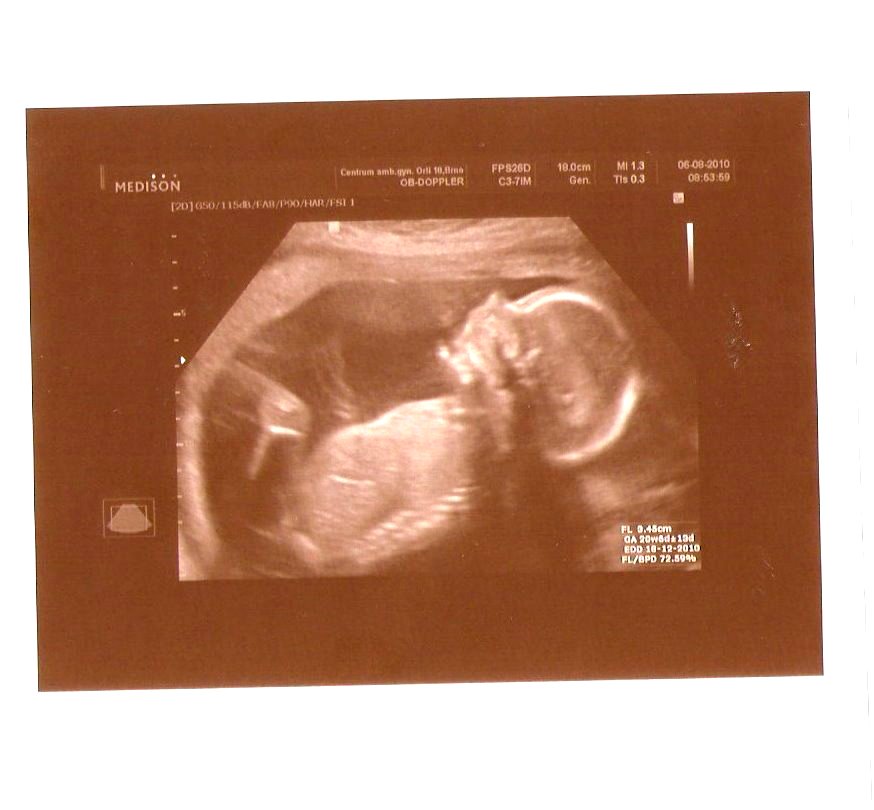

2.UTZ